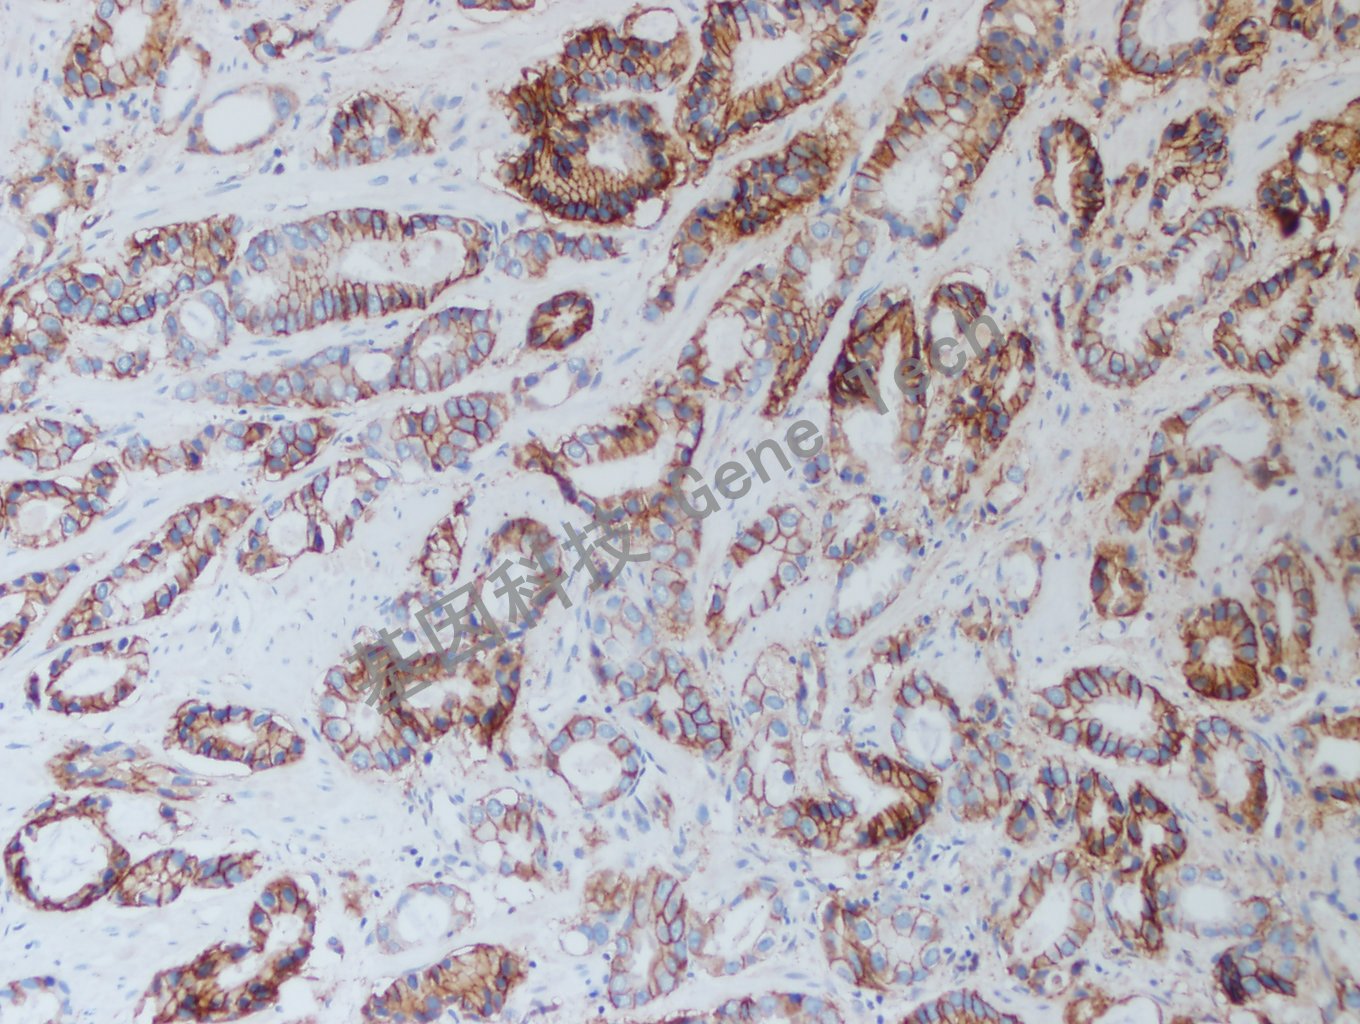

肺癌石蜡切片,用Claudin-7(GT2447)染色,细胞膜/细胞浆阳性,DAB显色。

结直肠癌石蜡切片,用Claudin-7(GT2447)染色,细胞膜/细胞浆阳性,DAB显色。

前列腺癌石蜡切片,用Claudin-7(GT2447)染色,细胞膜/细胞浆阳性,DAB显色。

肾癌石蜡切片,用Claudin-7(GT2447)染色,细胞膜/细胞浆阳性,DAB显色。